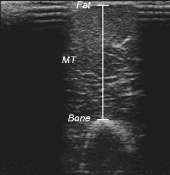

The researchers also made scans of the subjects' arms and used them to measure the increase in circumference of the biceps and triceps. There's a scan at the top of the page.